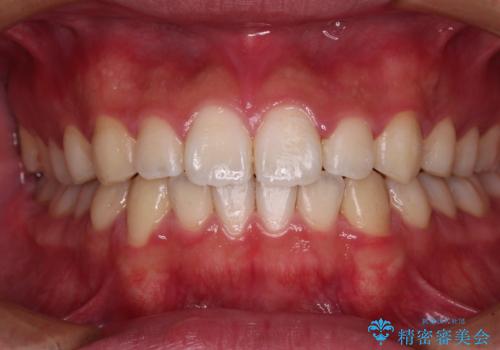

- 上下前歯の叢生を気にして来院された患者様です。

費用を抑え、期間もあまりかけずに治療をしたいとのことで、インビザライン・ライトを用いて矯正治療を行うこととしました。